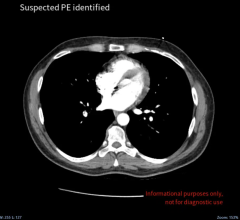

July 13, 2023 — New computed tomography (CT) technology allows for a comprehensive, simultaneous evaluation of lung ...